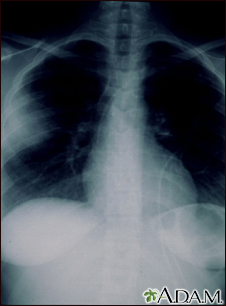

Aspergillosis - chest x-rayBackAspergillosis - chest x-rayAspergillosis is a fungal infection. The fungus invades and destroys tissue. This type of infection usually occurs in immunocompromised individuals. Here, a chest x-ray shows that the fungus has invaded the lung tissue. The lungs are usually seen as black areas on an x-ray. The cloudiness on the left side of this x-ray is caused by the fungus. E-mail FormEmail ResultsName:Email address:Recipients Name:Recipients address:Message: